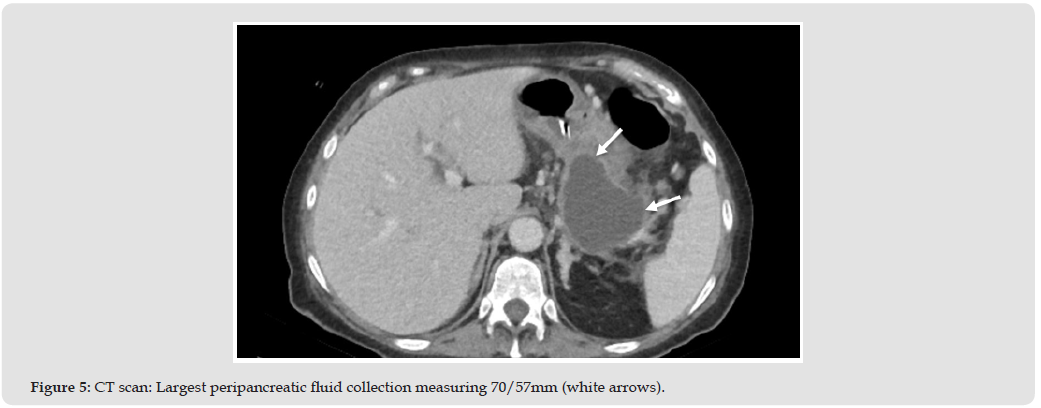

In the 12th day of hospitalization, the patient is transferred to the ICU as renal failure worsens also associating metabolic acidosis (meeting SIRS criteria for multiple organ dysfunction). During the stay in the ICU the patient receives hemodiafiltration, broad spectrum antibiotic is added as inflammatory blood markers are rising. Second CT scan is done 2 weeks after the first one at admission, showing worsening inflammation and necrosis of the pancreas, now present in the body and tail and enlarged fluid collections, however the duodenal inflammation is in regression (Figures 4 & 5). The patient is returned to the gastroenterology ward after 3 days, renal failure and acidosis resolved, abdominal pain improved significantly and normal calcium levels. The patient is transferred 10 days later to the surgery ward for further management. Surgery is done 7 days after the transfer, revealing parathyroid adenoma. Except for a short message 6 months after surgery stating patient is well, no further contact or reevaluation was made.